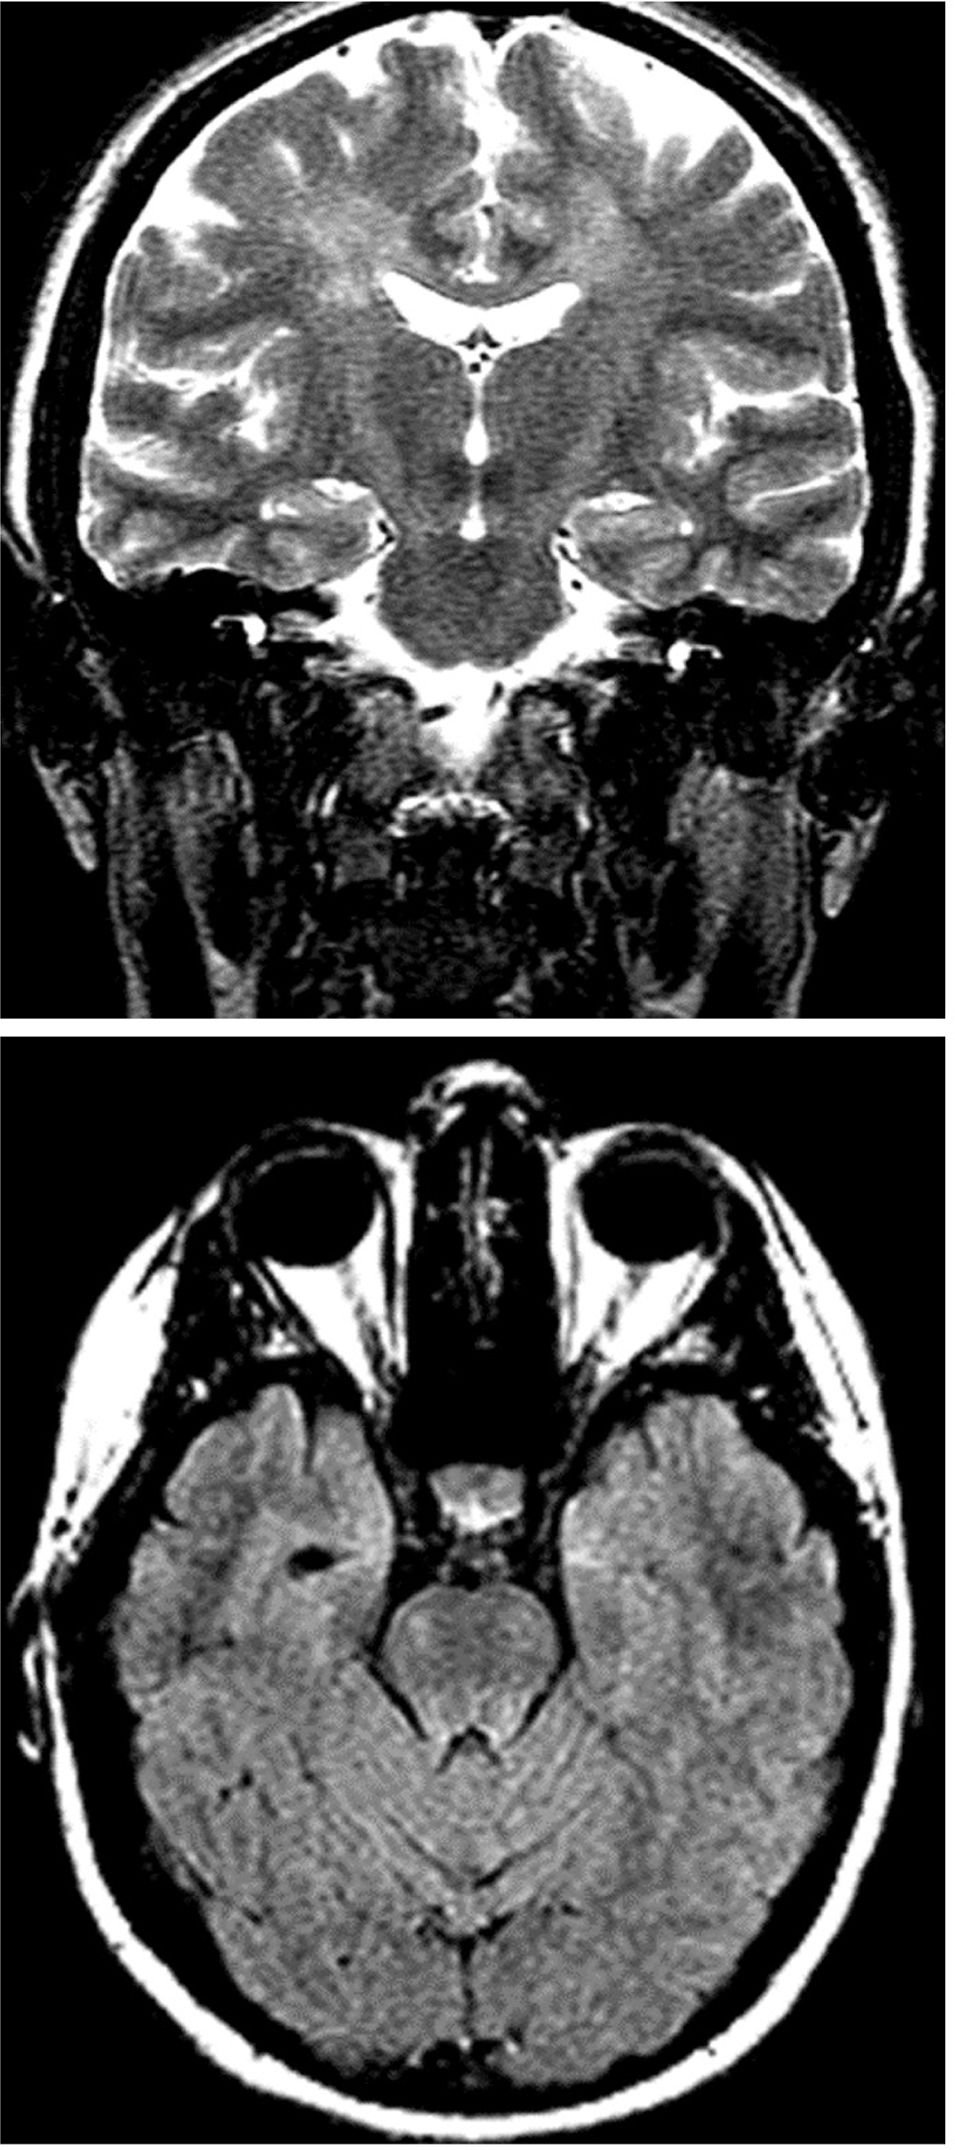

Pathologic studies in a limited number of cases have disclosed a relatively stereotyped pattern of reduced numbers of Betz cells in the frontal and prefrontal motor cortex, degeneration of the corticospinal tracts, also evident on MRI (Figure 3), and preservation of motor neurons in the spinal cord and brainstem (20).

Figure 3. T2-weighted coronal (3a, top) and FLAIR axial (3b, bottom) MRI showing signal changes that reflect Wallerian degeneration in the corticospinal tracts (Courtesy Dr. Rita G. Bhatia).

In patients with prominent corticospinal signs, the MRI may show slight atrophy of the motor cortex and signal changes indicating Wallerian degeneration of the corticospinal tracts (Figure 3). These changes may be diagnostically useful when the presence of severe LMN deficit makes pyramidal tract signs unobvious. Corticospinal tract degeneration appears as an increased FLAIR and T2 signal intensity in the posterior limb of the internal capsule, descending motor tracts of the brainstem, and spinal cord (13). These MRI signs however are generally subtle and often missed.